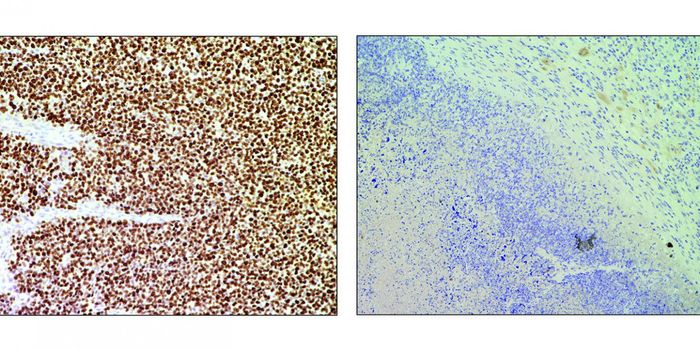

MAR 22, 2021ImmunologyImmunologists have identified a mechanism through which an oncogene mutation shields pancreatic tumors from immune cells ...